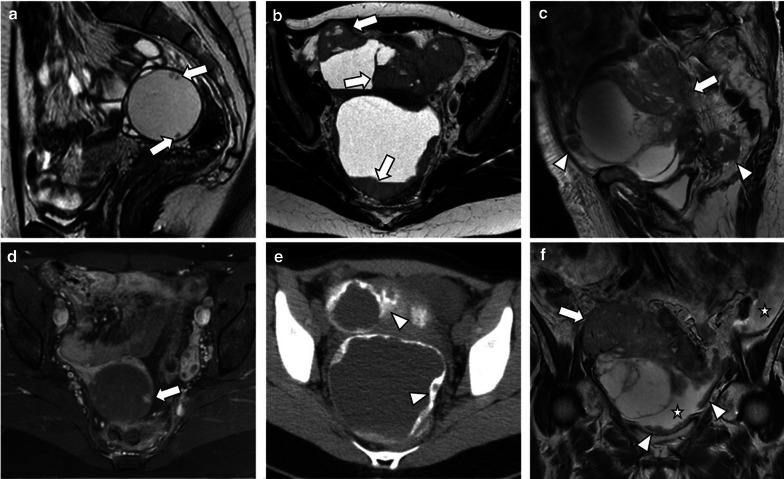

Three cases demonstrating the main radiological features of SBT, LGST and HGST. Sagittal T2-weighted image (a) and axial fat saturation T1-weighted image after gadolinium administration (d) reveal a right unilocular cystic tumour with well-defined margins and small enhancing papillary projections (arrows). Histologic examination was compatible with SBT. Axial T2–weighted MR image (b) and axial unenhanced CT image (e) show a bilateral mixed LGST with solid parietal components (arrows) and calcified psammoma bodies (arrowheads). Sagittal and coronal T2-weighted images (c and f) demonstrate a bilateral mixed HGST with irregular contours and exuberant solid components (arrows). Several abdominal (not shown) and pelvic peritoneal metastases (arrowheads) and ascites (stars) were noted

Macroscopically, LGSC may present as bilateral adnexal tumours, often multicystic with nodular areas, excrescences, and papillary projections on the interior surface (Fig. 1). Some may be gritty due to the presence of calcifications [3].

LGSC can typically appears on CT as a large, complex, cystic mass with well-marginated septa, papillary projections, and solid components that may be found unilaterally or bilaterally [1, 2, 10, 17] (Figs. 4, 5, 6, 7). The number and complexity of serous tumours on solid tissue correlate with malignancy risk [17].

Peritoneal metastases, nodal calcifications, papillary projections in cystic lesions, and the presence of necrosis are findings that suggest malignancy and help to distinguish malignant serous tumours from benign lesions [1, 4, 17]. Ascites is also rarely identified in LGSC, whereas HGSC typically presents abundant ascites and diffuse peritoneal metastases (Figs. 6, 7) [1, 4, 8].

Malignant serous tumours are less frequently cystic compared to borderline (respectively 25% and 44%). They tend to be complex mixed lesions with indistinct solid-cystic interfaces [8] (Figs. 1, 3, 4, 7, 9).

It is known that the number of papillary projections and solid components increases from SBT to LGSC and to HGSC [8]. On ultrasound, LGSC usually appears as a multilocular cystic lesion with a higher number of solid components when comparing to SBT and with a lower number of solid components when compared to HGSC [1, 8, 10, 14] (Fig. 3). Calcifications corresponding to psammoma bodies are common in LGSCs and can be identified on ultrasound [3, 8]. On the other hand, HGSC appears more frequently as a non-papillary solid mass with areas of cystic change, necrosis, and/or haemorrhage [1, 10].